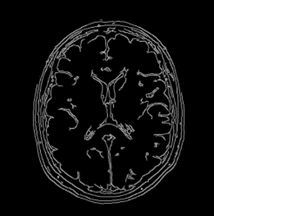

d) Ảnh sau khi thực hiện phân đoạn dựa trên cạnh

Hình 3 : Ảnh sau khi sử dụng kỹ thuật phân đoạn dựa trên cạnh